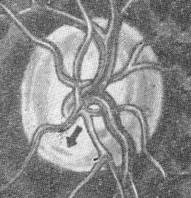

Tensiunea intraoculara crescuta determina tulburari circulatorii la nivelul capului nervului optic (Fig. 13.5). Lipsa de nutrire a fibrelor nervoase produce atrofia optica, iar lipsa de nutritie a tesutului glial de sustinere realizeaza excavatia papilara.

Fig. 13.5 - Vascularizatia nervului optic

(ACR -artera centrala a retinei, VCR - vena centrala a retinei, R-retina, C-coroida, S-sclera, DO-disc optic, D-dura mater, A-arahnoida, Pia - pia mater, NO -nerv optic, SA-spatiu subarahnoidian, Rcol-ramuri colaterale, DO- disc optic, APC- artere ciliare posterioare)